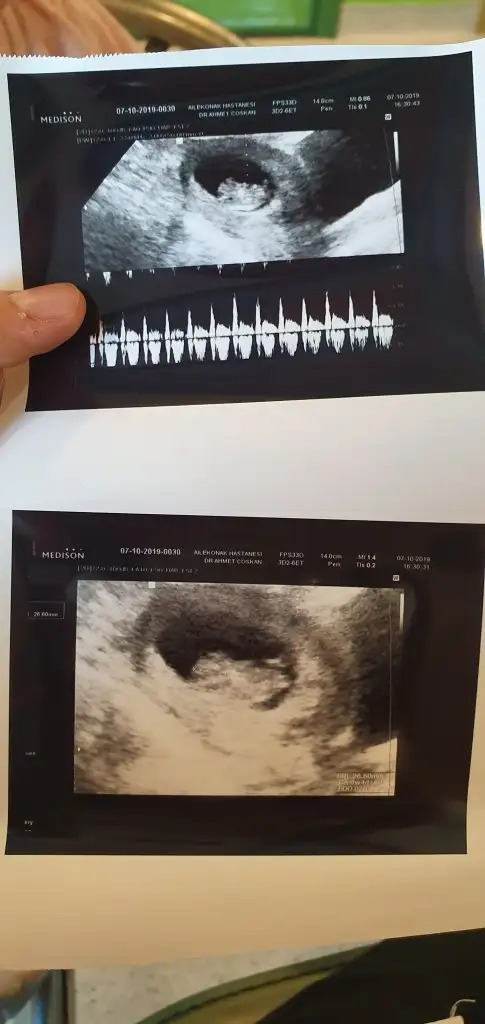

dr soylemeden siz gorun genital nub teorisi ( bebegin cinsiyeti)

Kizlar sizce ne cinsiyeti

Bize de kiz gibi dedi doktor ama net degil